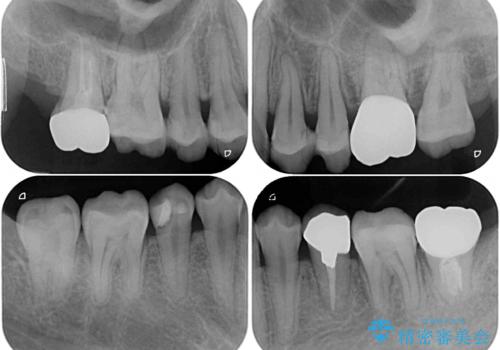

- 虫歯が多く、セラミッククラウンにより虫歯治療を行っている途中で矯正治療をしたいとのことで来院された患者様です。

上顎前歯が舌側に転位しており、なるべく早く楽に矯正したいとのことで、ワイヤー矯正を行うこととしました。

虫歯治療途中の歯は仮歯が装着されていたため、そのまま矯正治療を行い、矯正後に補綴治療を行うこととしました。

インビザライン矯正では苦手とする舌側転位した前歯をスムーズに改善することができました。

矯正治療により歯磨きがしやすくなったので、虫歯予防のセルフケアが行いやすい環境となりました。